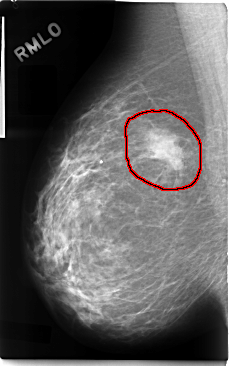

C_0094_1.RIGHT_MLO

RIGHT_MLO LINES 4752 PIXELS_PER_LINE 2968 BITS_PER_PIXEL 12 RESOLUTION 50 OVERLAY

FILE: C_0094_1.RIGHT_MLO.OVERLAY

TOTAL_ABNORMALITIES 1

ABNORMALITY 1

LESION_TYPE MASS SHAPE IRREGULAR MARGINS ILL_DEFINED

ASSESSMENT 5

SUBTLETY 5

PATHOLOGY MALIGNANT

TOTAL_OUTLINES 1

BOUNDARY